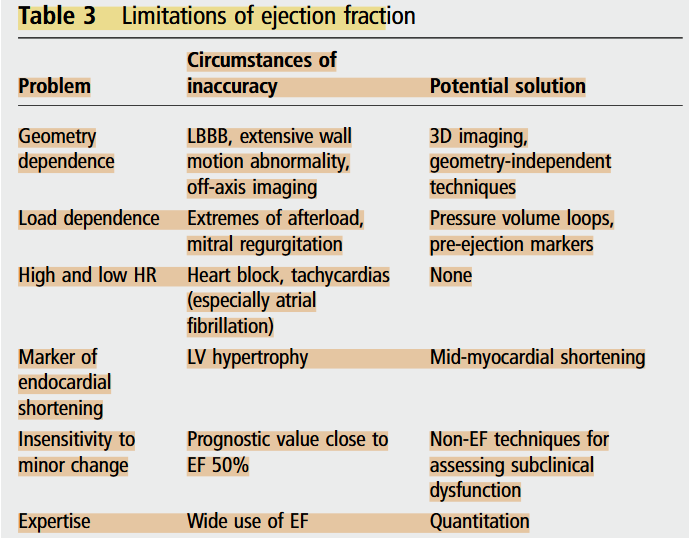

However, LVEF still has a number of important limitations and may provide suboptimal evaluation. Firstly, the ejection fraction is load-dependent, meaning that it cannot be interpreted as a reflection of contractility in the absence of knowledge about afterload and preload. Instead, the performance of a pressure-volume loop may better facilitate the understanding of contractility (Marwick, 2013). In addition, the ejection fraction is influenced by heart rate. The increased stroke volume associated with bradycardia may lead to overestimation of the true ejection fraction, and conversely in tachycardia, the reduced stroke volume may lead to underestimation of the actual function (Marwick, 2013).

EF has a number of important limitations

Marwick, T. H. (2013). Methods used for the assessment of LV systolic function: Common currency or tower of Babel? Heart, 99(15), 1078–1086. https://doi.org/10.1136/heartjnl-2012-303433

EF AND VOLUMES. In general, left ventricular ejection fraction (LVEF) is more useful than stroke volume as a marker of LV function, because it takes into account the Frank-Starling relationship.

LVEF is mainly affected by preload, afterload, and contractility,

WHAT EF HIDES. A major limitation of EF is that it is sometimes a source of disproportionate focus, to the exclusion of other features.

Marwick, T. H. (2018). Ejection Fraction Pros and Cons. Journal of the American College of Cardiology, 72(19), 2360–2379. https://doi.org/10.1016/j.jacc.2018.08.2162